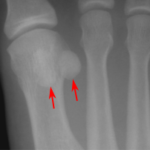

Each person has two sesamoid bones in each foot, located in the ball of a person’s foot, underneath their big toe joint. These two pea-sized bones are embedded in a specific tendon and help act as a pulley for the tissue when you flex or curl you big toe. They also help to handle stress […]

Your sesamoid bones are a small section of bones that are embedded in a tendon in your foot. More precisely, they are two pea-sized bones that are located in the ball of a person’s foot, beneath their big toe joint. They act as pulleys for the tendons and help a person flex and curl their […]